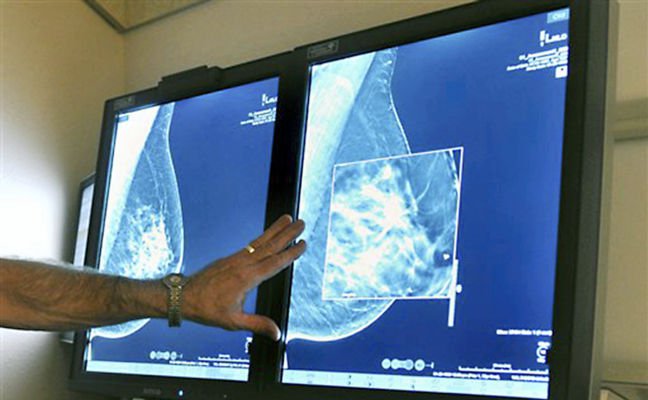

Mammograms Increase Risk Of Breast Cancer, Here Are The Safe Alternatives For Breast Exams

You may have heard that mammograms, the tests that are commonly used to detect breast cancer, can actually increase the risk cancer. Well, you’re not wrong! Yet, these breast screenings are considered to be the most effective form of detecting breast cancer, at least according to the Center For Disease Control (CDC). There’s actually an overwhelming amount […]